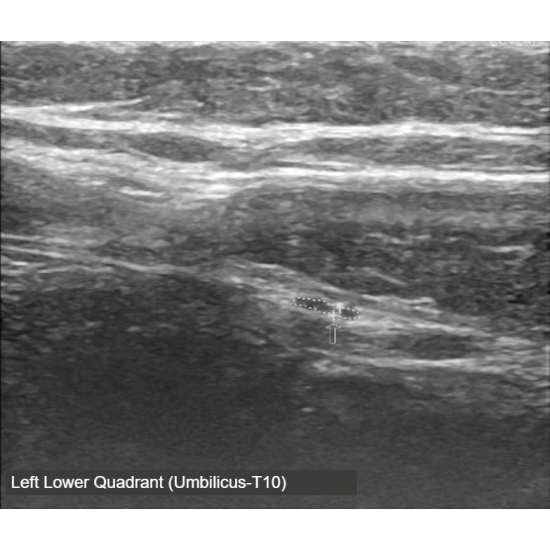

Pelvis ultrasound, CT abdomen/pelvis, MRI abdomen/pelvis and MRI total spine were performed and showed no evidence of acute pathology. The patient underwent a diagnostic ultrasound in clinic which revealed signs of anterior cutaneous nerve entrapment, including hourglass narrowing, loss of echotexture and enlargement of the nerve at the level of entrapment. Ultrasound images included below demonstrate the difference in cross sectional area between the left and right anterior abdominal cutaneous nerve, respectively; note the slight variation in the course of the nerve as it traverses the fibrous band within the rectus abdominis.

Case Photo #1 , Case Photo #2